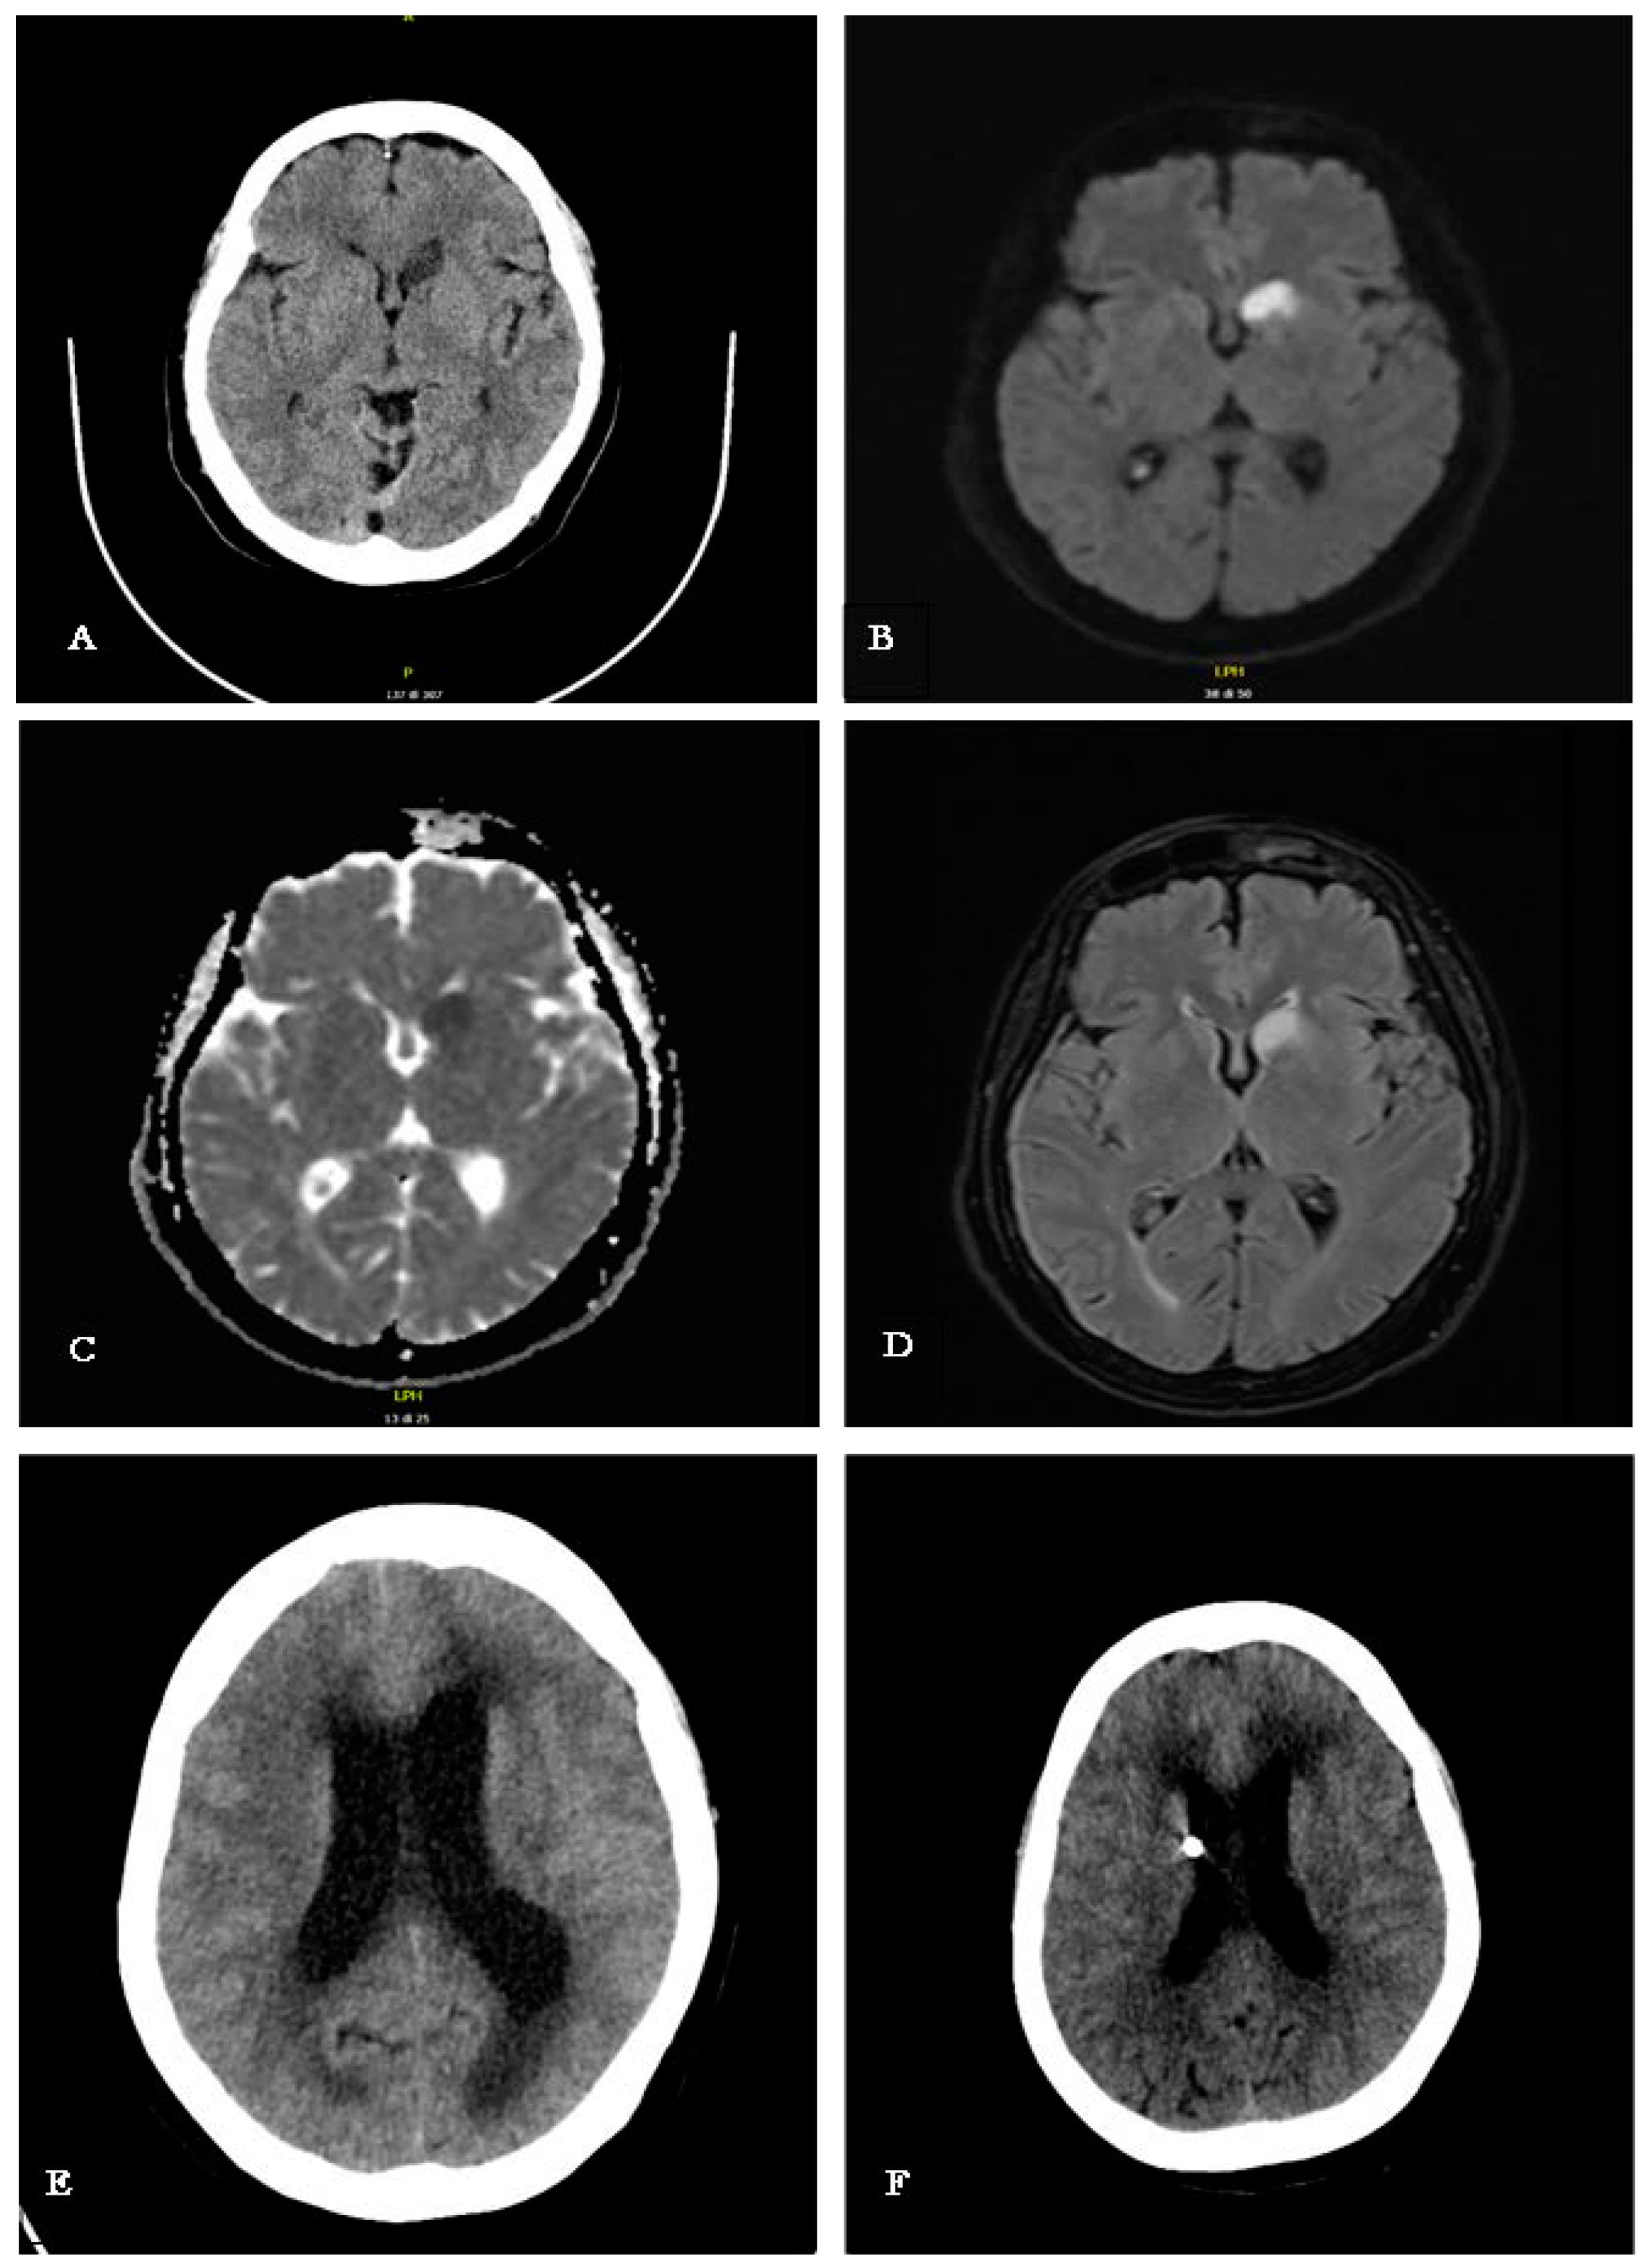

Upon presentation to the emergency room, vital signs, including blood pressure, heart rate, and oxygen saturation, were within normal limits. The patient exhibited fever of 39 °C, and neurological examinations revealed a persistent headache, mild ideomotor slowing, abulia, and multidirectional oscillations during gait and the Romberg test. The rest of her clinical examination was unremarkable, with no observable focal neurological deficits, although a potential language barrier may have constrained the neurological assessment. A computed tomography (CT) of the brain revealed an ischemic lesion on the head of the left caudate nucleus (Figure 1A). Subsequently, Magnetic Resonance Imaging (MRI) confirmed a restricted signal in DWI/ADC corresponding to the lesion site, with hyperintensity in FLAIR sequences indicative of a subacute ischemic lesion (Figure 1B,D). Additionally, there was no alteration in the blood–brain barrier after contrast medium administration, and the Time-of-Flight Magnetic Resonance Angiography study documented regular flow signals from the major intracranial arterial vessels in the absence of significant dilations/stenosis (Figure 1B–D). Accordingly, aspirin was administered for the secondary prevention of ischemic stroke. Comprehensive cardiovascular investigations, including echocardiography and Doppler ultrasonography of the supra-aortic trunks, revealed no abnormalities.

Figure 1.

(A) CT scan performed upon arrival in the ED, showing hypodensity in the left caudate nucleus; (B–D) MRI scan (DWI, ADC, FLAIR) performed the day after the patient’s admission in the ED, confirming a subacute ischemia in the left caudate nucleus; the Angio-RM TOF study documented regular flow signal from the major intracranial arterial vessels in the absence of significant dilations/stenosis (these sequences are not shown here); (E) CT scan performed during neurological clinical worsening, with a significant decline in consciousness, showing marked dilation of the ventricular system both supra and infratentorial, along with hypodensity of the subependymal white matter, indicating acute communicating hydrocephalus with transependymal CSF reabsorption; (F) CT scan performed after the insertion of the EDV. This intervention led to a rapid improvement in the patient’s clinical status and a modest reduction in the size of the lateral ventricles.

CSF samples were sent for bacterial culture, microscopy, and film array testing, along with Polymerase Chain Reaction (PCR) for Mycobacterium tuberculosis, given the patient’s geographic background. The PCR test confirmed tuberculosis, leading to a diagnosis of tubercular meningitis. Treatment was promptly initiated with rifampicin, isoniazid, ethambutol, pyrazinamide, and linezolid, alongside dexamethasone at 0.4 mg/kg/day [2,3]. Despite the initiation of antitubercular therapy, unexpected and rapid neurological deterioration was observed. A new CT scan of the brain was performed, detecting the presence of acute hydrocephalus (Figure 1F). Hence, an external ventricular drain (EDV) was placed, and follow-up CT scan showed a reduction in ventricular volume and size (Figure 1E).

The day after initiating treatment, the patient’s condition rapidly deteriorated, with a significant decline in consciousness, becoming responsive only to painful stimuli. An emergency brain CT scan revealed significant ventricular dilation in both supratentorial and infratentorial regions, with subependymal white matter hypodensity, indicating acute communicating hydrocephalus with trans-ependymal CSF absorption. An external ventricular drain was urgently placed, resulting in rapid clinical improvement and a modest reduction in lateral ventricular size on subsequent CT imaging (Figure 1E).

To address this critical condition, a neurosurgical procedure was performed to insert an external ventricular drain. This intervention led to a rapid improvement in the patient’s clinical status and a modest reduction in the size of the lateral ventricles on a follow-up CT scan (Figure 1F).